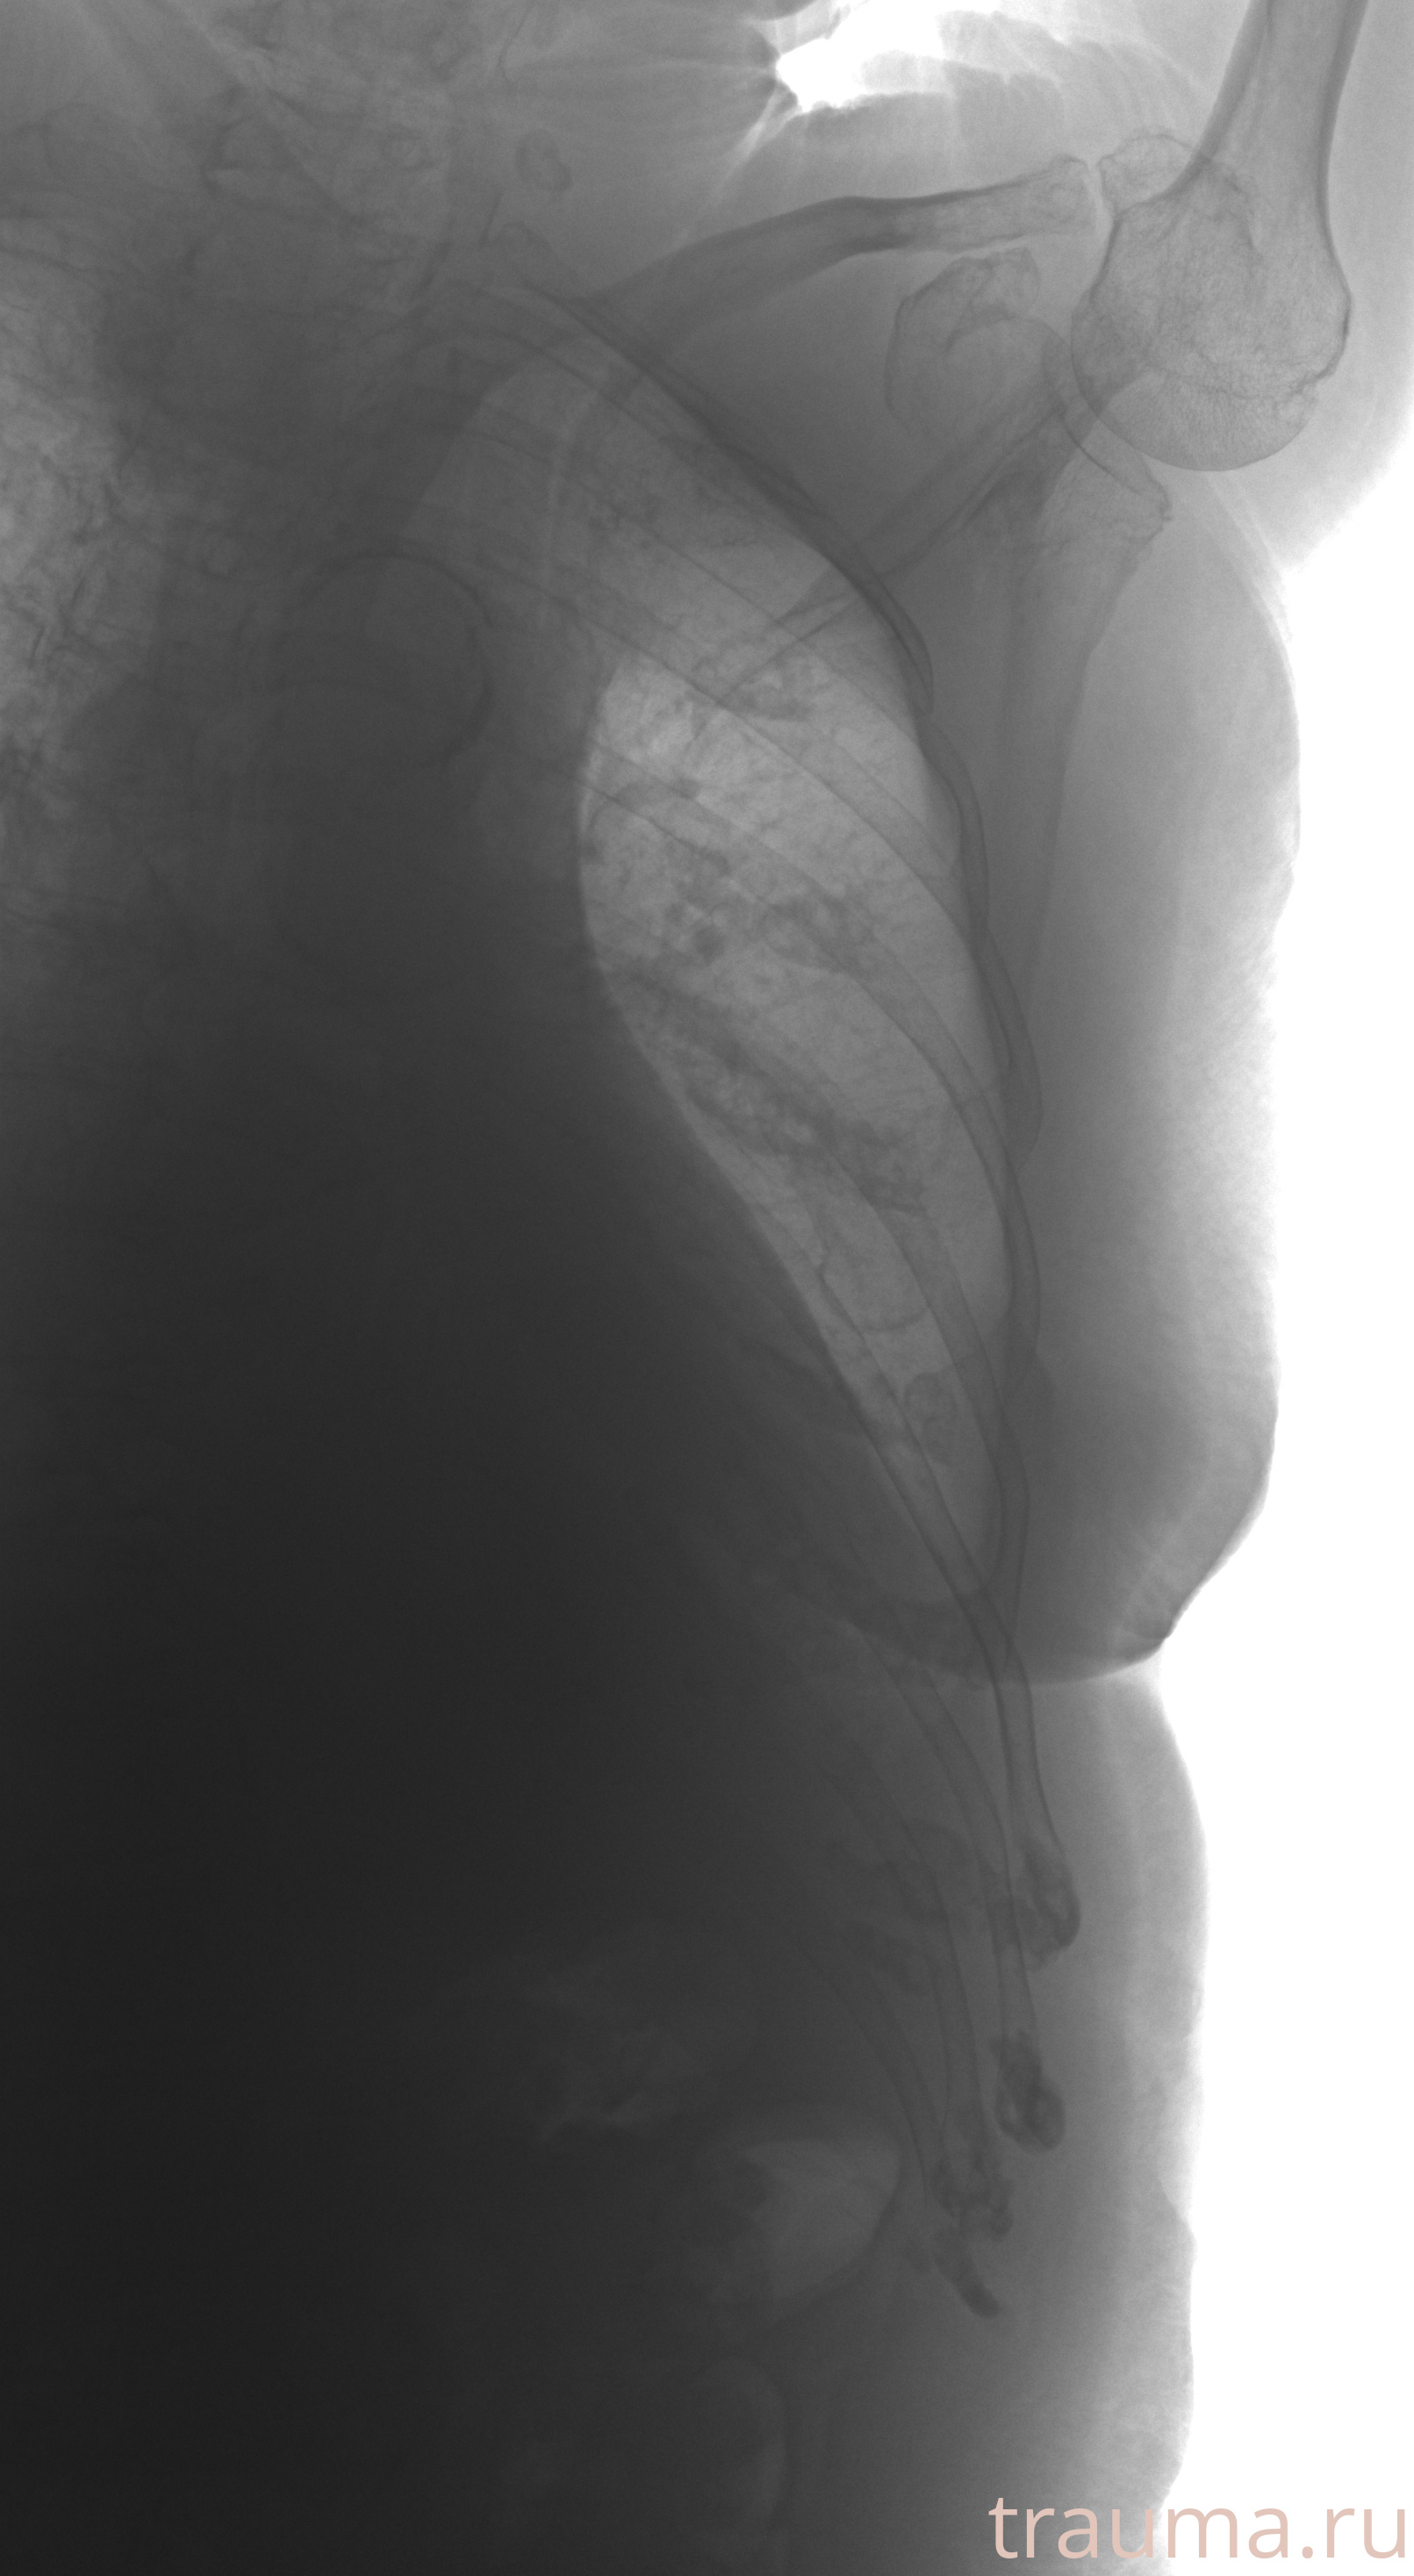

Рентгенограммы

Рентген на дому: по вашему адресу приезжает врач-рентгенолог, травматолог-ортопед с мобильным рентгеновским аппаратом, проводит диагностику травмы или заболевания, делает необходимые рентгенограммы, дает рекомендации по дальнейшему лечению. Получить качественные снимки в домашних условиях возможно благодаря уникальной методике, разработанной МосРентген Центром для института  Склифосовского

при переломе шейки бедра и пневмонии от компании МосРентген Центр - партнера Института имени Склифосовского